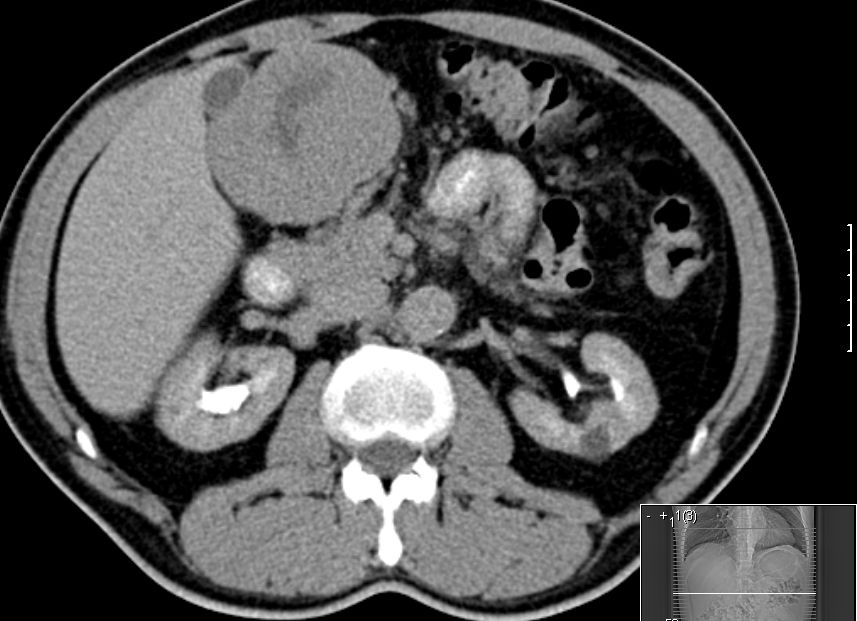

84-jährige Frau mit symptomatischer Anämie (Hb 3,8) und Kachexie (BMI 16).

Palpable Resistenz im Epigastrium.

Intraoperativ fand sich im Mesenterium des Jejunum eine 4cm große knotige Raumforderung.

Histologisch gastrointestinaler Stromatumor. Exzision im Gesunden. Ki67 = 1 % (niedriges Risiko).![]() |